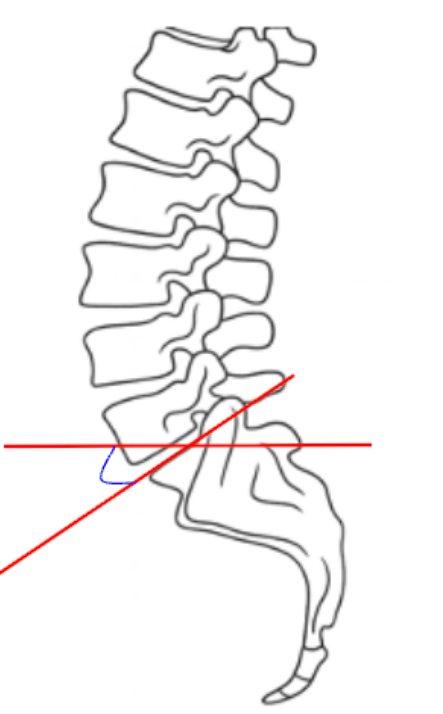

The Lumbosacral Angle (Ferguson’s Angle)—also known as the Sacral Inclination—is a sagittal alignment parameter that quantifies the inclination of the sacrum relative to the horizontal plane.

• Draw a line along the superior endplate of S1—this represents the sacral base.

• Draw a horizontal reference line (parallel to the bottom edge of the image).

• Measure the angle formed between the sacral base line and the horizontal line—this is the Lumbosacral (Ferguson’s) Angle.

• The angle opens anteriorly (downward toward the front of the body).